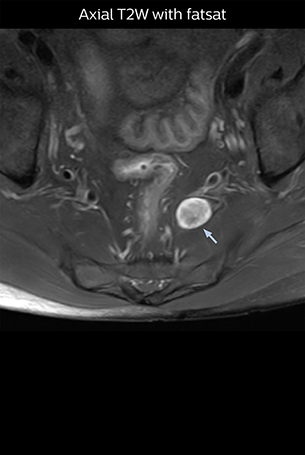

“Before NerveVIEW, diagnosis by MRI alone was sometimes difficult, unless there was a strong suspicion based on clinical symptoms,” says Shoji Yabuki, MD, DMSc, Orthopedic surgeon at Fukushima Medical University School of Medicine. “This is why we routinely perform selective lumbosacral radiculography (nerve root block) and x-ray in such cases. However, radiculography can only depict nerves as far as the contrast agent reaches. When a nerve is distorted by compression, the contrast agent will not pass through this compressed area, preventing us from evaluating the full nerve compression.”

“In such case, we would then browse through axial T2-weighted MR images slice by slice and mentally reconstruct the actual situation based on both radiculography and MRI. Fortunately, NerveVIEW can now very well show nerve courses and presence of nerve compression or edema in one single image series.”

According to Tanji, methods such as ProSet FFE, STIR or 3D VISTA are anatomically nonselective because background signals, for instance from blood vessels, often interfere with nerves, which hampers evaluation of details, especially at the peripheral side of the nerves.

“The intra-luminal signal of veins, especially around the intervertebral space, can be suppressed well with NerveVIEW. As a result, we can easily observe the detailed nerve structure around the posterior ganglion,” he says. “This is why we use 3D NerveVIEW for intraforaminal stenosis and extraforaminal stenosis/herniation (lateral disc herniation). On the other hand, if herniation is suspected to exist inside the dorsal root ganglion (DRG), balanced TFE or ProSet-FFE is applied. NerveVIEW is not suitable for evaluating the median type of herniation.”

The SE-EPI DWI-based method for MR neurography works well for large FOV exams like whole-body MRI, but focal examination of nerves is often limited by the attainable spatial resolution (both inplane and slice direction) and geometric distortion. “3D NerveVIEW achieves higher in-plane resolution – close to our other routine spine sequences – and the source images can be used instead of adding a fat-suppressed T2-weighted sequence,” Tanji says.